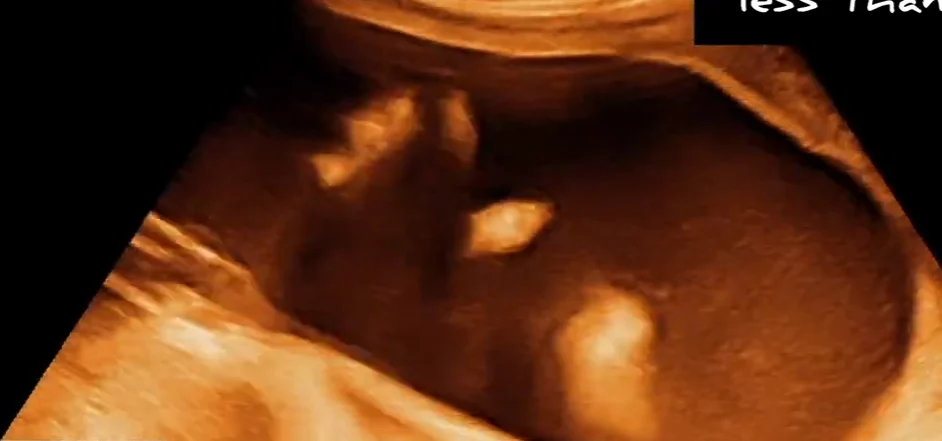

Tai đóng thấp (Low-Set Ear)

• Tai đóng thấp (Low-Set Ear)